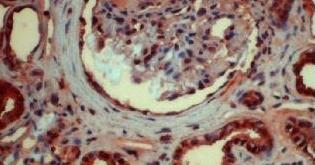

下圖為腎樣本中咪唑啉酮著色的AGE

AGE是糖尿病早期風險測評的重要生物標志。

在胰島素抵抗(IR)、糖調節(jié)受損IGR(和糖尿病者體內),AGE加速形成。產生的過量AGE通過直接或間接作用,導致多種病理反應,成為糖尿病并發(fā)癥的重要致病因素。